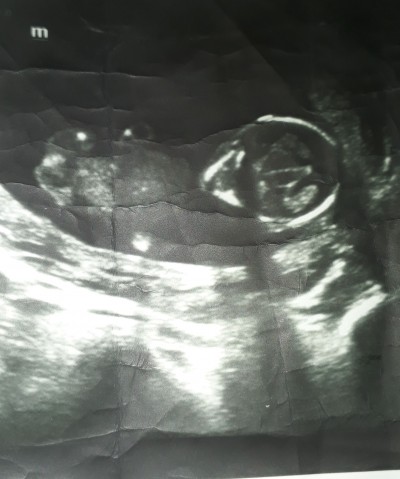

Arkadaşlar yaşıma bağlı down sendromu riski vardı yakında amniyosentez düşünüyorum bebeğin kafa bölgesi büyük geldi gözüme korktum siz ne düşünüyorsunuz

Gebelik haftası 15

Ultrasonda oyle cikiyor oldugundan daha buyuk cikiyor.

12 haftalıkken normal duruyordu canm şimdi 14 buçuk yani 15 e girdi böyle oldu görüntüsü

Amniyosentez hiç yaptırma sakın 35 yaşından sonra herkeste çıkıyor o. Hiç gerek yok öyle şeylere. Başı da ultrasonda büyük gibi görünmesi normal

O ultrasonda anlaşılmaz ki doktor ölçünce belli olur, zaten bebeklerin kafası biraz büyük olur anne karnında beyin gelişimi olduğu için